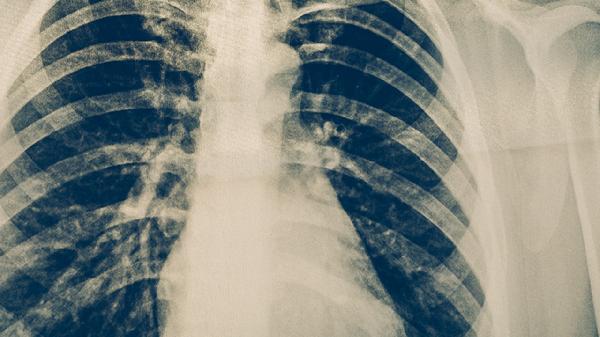

肺炎患者可遵医嘱使用阿莫西林胶囊、头孢克肟分散片、盐酸左氧氟沙星片、阿奇霉素片、氨溴索口服溶液等药物缓解症状。肺炎通常由细菌、病毒感染或吸入性损伤等因素引起,需根据病原体类型选择针对性药物,同时配合止咳化痰、退热等对症治疗。